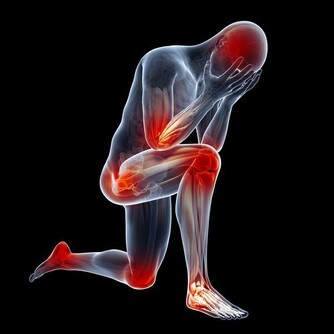

3、關節老化

人的關節就好比輪胎,用久了會慢慢磨損。

中年時過度的勞累,伴隨體重的不斷增加,

對關節造成了更大的壓力,加重了關節的老化,重者甚至出現腫痛,發生關節炎等。